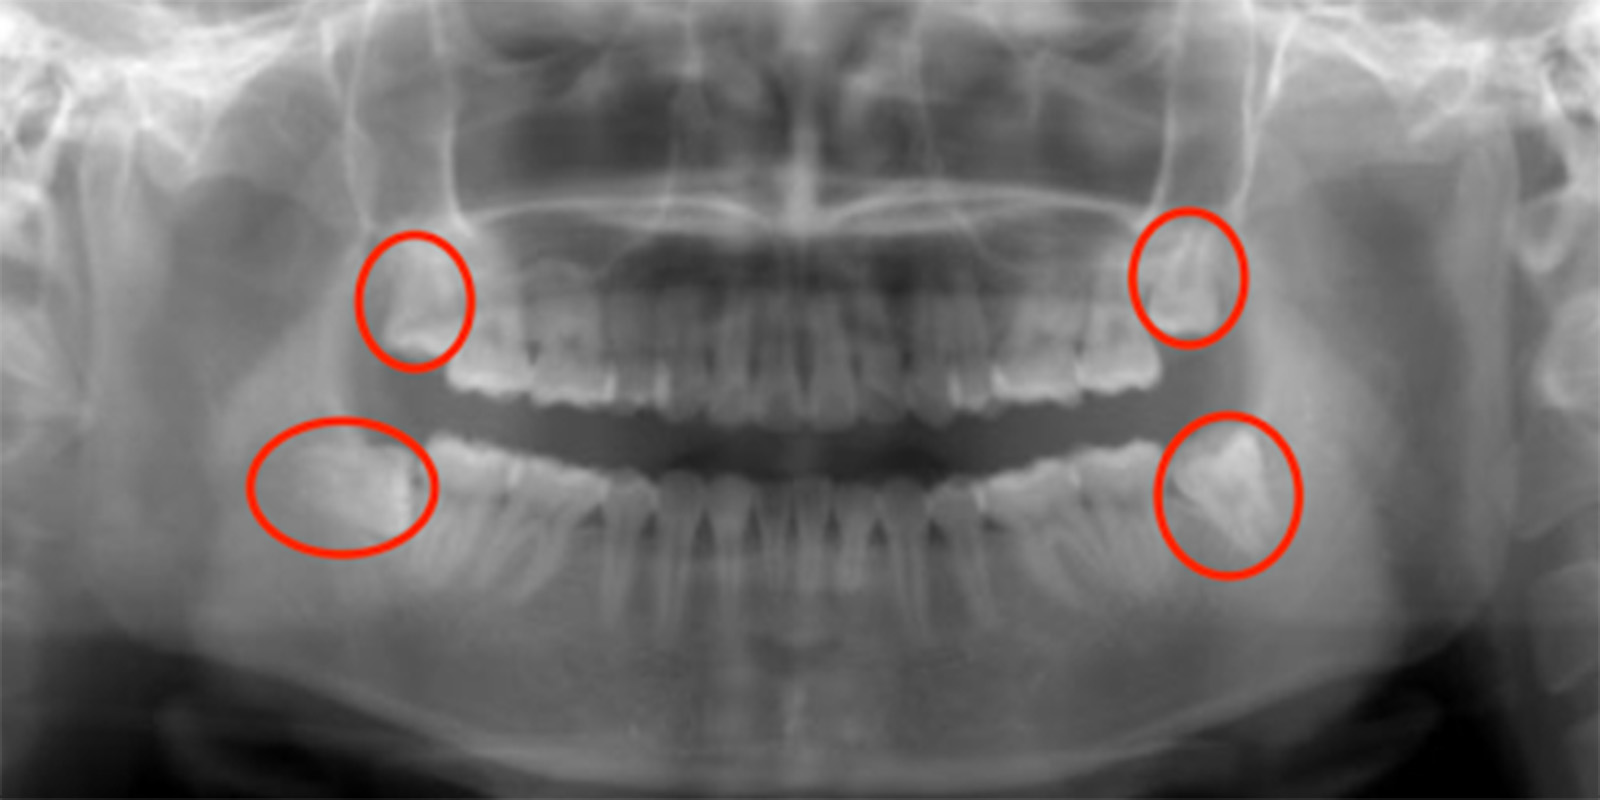

レントゲン画像の親知らず

親知らずがあるレントゲン画像